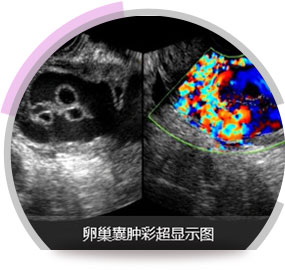

河南医药院专家董长江教授耐心的接待并做了详细检查,彩超、子宫输卵管造影及宫腹腔镜检查。

彩超检查证实盆腔左侧有一直径4*5cm卵巢囊块,呈一中高回声表现,确诊卵巢囊肿,子宫输卵管造影发现其子宫内低回声,有5*6cm巨大肿瘤,确诊子宫肌瘤,且患者有高血压。